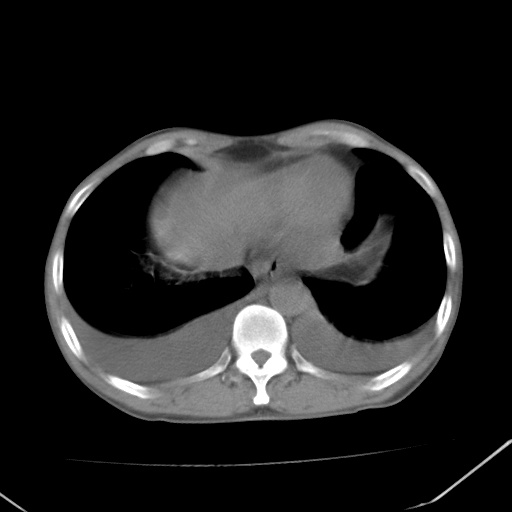

男、42岁、咯血3天。既往有甲亢、贫血、血尿蛋白尿史多年。血象:wbc:6.   中性粒:70.6%。

结合病史考虑双肺泡积血,双侧胸腔少量积液;肺水肿待排(肺水肿症状重)。

双肺堆成磨玻璃影,双测胸腔积液。考虑:肺水肿、间质性肺炎、真菌感染、ards、hiv感染、肺出血。

双肺野对称性磨玻璃影,分布于内中带,双侧胸水,患者有咯血。

双肺野广泛对称性磨玻璃影、实变影,以肺门为中心,主要分布于内中带,符合典型肺泡性肺水肿;伴双侧胸腔少量游离积液。结合患者既往病史且咯血就诊,支持多因素(尿毒症等)所致之肺水肿、肺出血、胸水;影像表现暂不考虑心源性水肿,且症状也不太符。需密切随诊结合临床治疗等进一步明确。

心影增大密度略低,双肺磨玻璃样高密度影及双侧胸腔积液,考虑心功能不全继发双肺肺水肿及双侧胸腔积液。心影密度略低,考虑贫血所致。